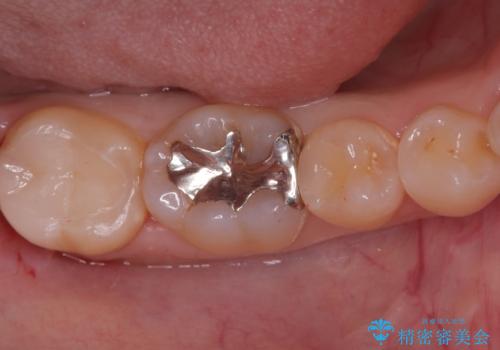

奥歯の銀歯を自然に!右下6番のメタルフリー治療

- 右下6番の奥歯に入っている金属の詰め物(メタルインレー)を気にされてご来院されました。お口の中の金属をなくしたいという患者様のご希望と、見た目の改善を目指し、天然歯に近い色と質感を持つセラミックインレーに交換する治療計画を立案しました。これにより、審美性の向上と、金属アレルギーのリスクがないメタルフリーの環境を実現することを目指しました。

治療では、まず古い金属のインレーを慎重に取り外し、内部に虫歯の再発がないかを丁寧に確認しました。歯を最小限だけ形成した後、精密な型取りから患者様の歯の色に合わせたオーダーメイドのセラミックインレーを作製しました。セラミックは、歯質との適合性が高く、プラークが付着しにくいため、虫歯の再発リスクを抑えるメリットもあります。適合性の高いセラミックインレーを装着することで、長年のコンプレックスだった銀歯がなくなり、機能的にも安定した自然な奥歯を取り戻していただけました。